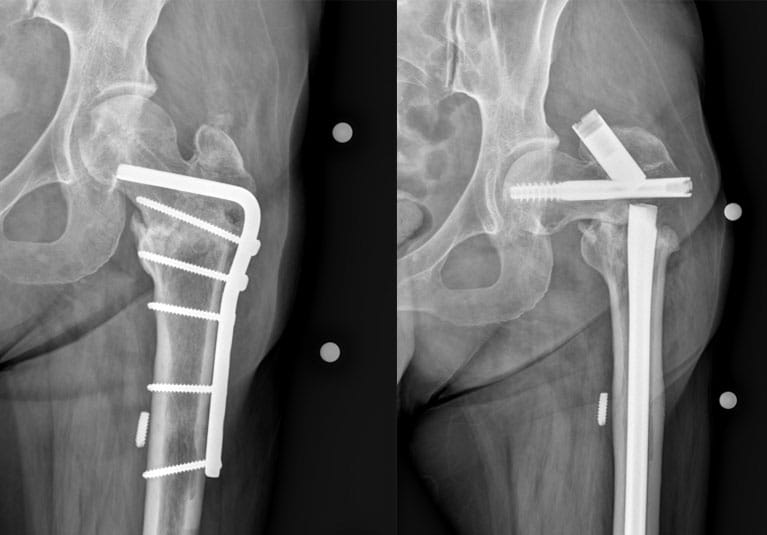

Proximal femur nonunion with hardware failure

Repair of left proximal femur nonunion with hardware failure